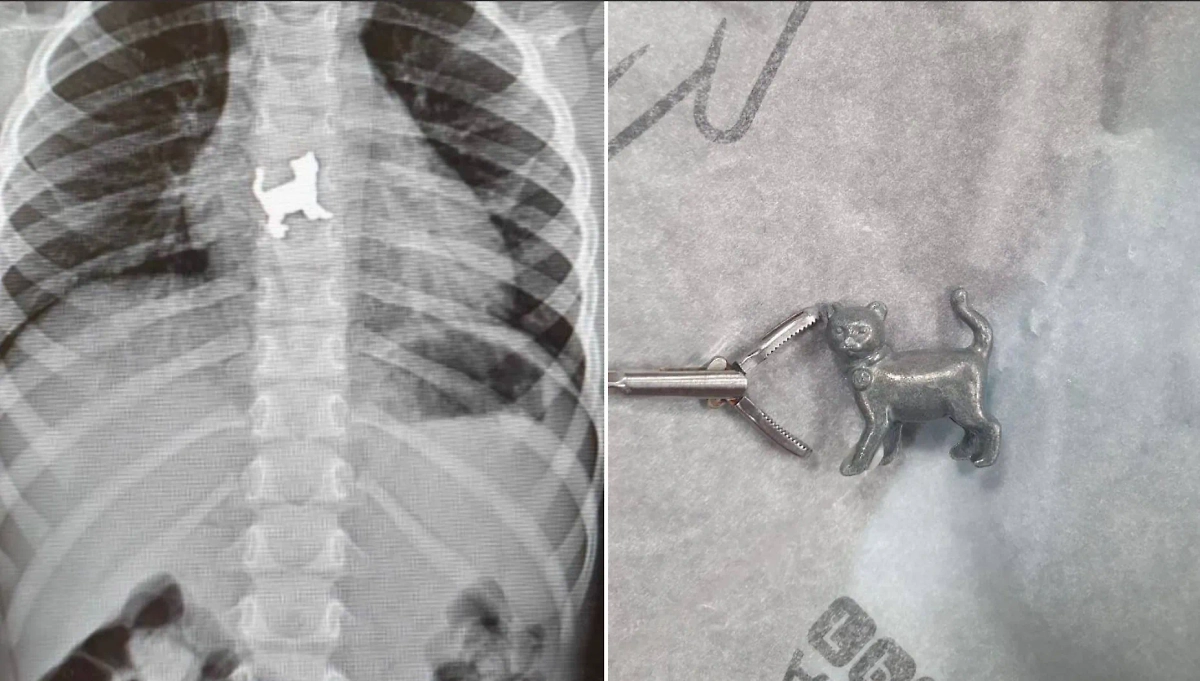

В Уфе трёхлетняя девочка во время игры проглотила металлическую игрушку в форме котёнка, с болями в груди её доставили в больницу. Об этом рассказал министр здравоохранения Башкирии Айрат Рахматуллин.

"Пациентку госпитализировали в хирургическое отделение, где провели ригидную эзофагоскопию и удалили инородное тело", — пояснил Рахматуллин. Сейчас с девочкой всё в порядке.